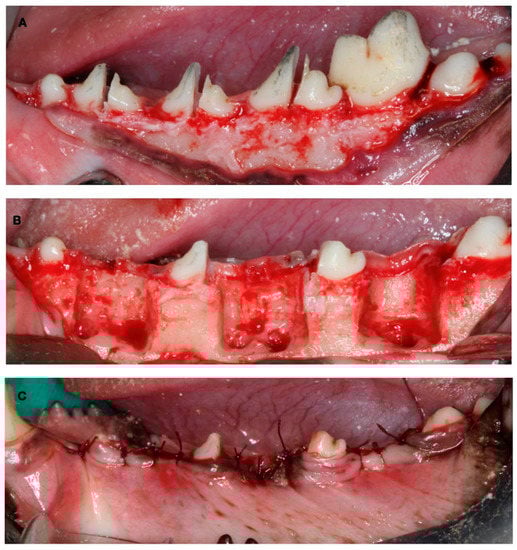

2.2. Surgical Interventions

- The test group using deproteinized bovine bone mineral (DBBM) (BioOss®, Geistlich Pharma, Wolhusen, Switzerland) combined with a synthetic polylactic membrane (PLAB) (GUIDOR®, Sunstar, Schlieren, Switzerland)

- The positive control group using DBBM (BioOss®, Geistlich Pharma, Wolhusen, Switzerland) combined with a natural porcine collagen membrane (NPCM) (BioGide®, Geistlich Pharma, Wolhusen, Switzerland)

- The negative control group using only the synthetic polylactic membrane (PLAB) (GUIDOR®, Sunstar, Schlieren, Switzerland)